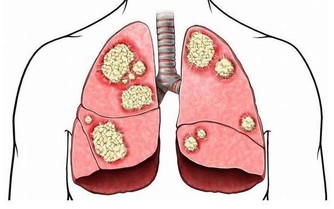

幽門桿菌是寄宿在胃裡的微生物,肉眼看不到,如果有條件去檢查,

在顯微鏡下,就能看到密密麻麻的幽門桿菌,甚是是可怕。